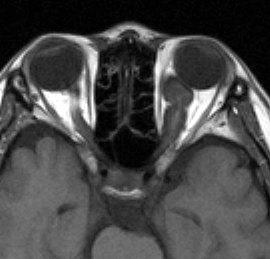

- 子供に見られる視神経膠腫は頻度の高いもので,NF-1の4%に発生します

- 下の図のように眼窩の中の視神経が腫瘍になることもありますし,視神経交叉といって両方の視神経が合わさった場所にできるものもあります。視神経膠腫はとても小さい子供にできて視力が下がりますが,手術で摘出することはできません。でも,とってもゆっくり大きくなり,ある程度の年齢になると大きくなるのが止まってしまいます。手術以外の治療法は毛様細胞性星細胞腫(クリック)のところに書いてありますから読んで下さい。